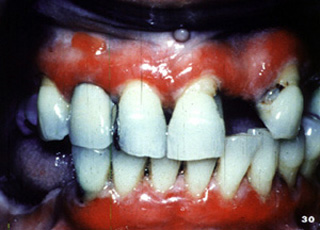

Aquí hay  áreas de ulceración y descamación gingival.